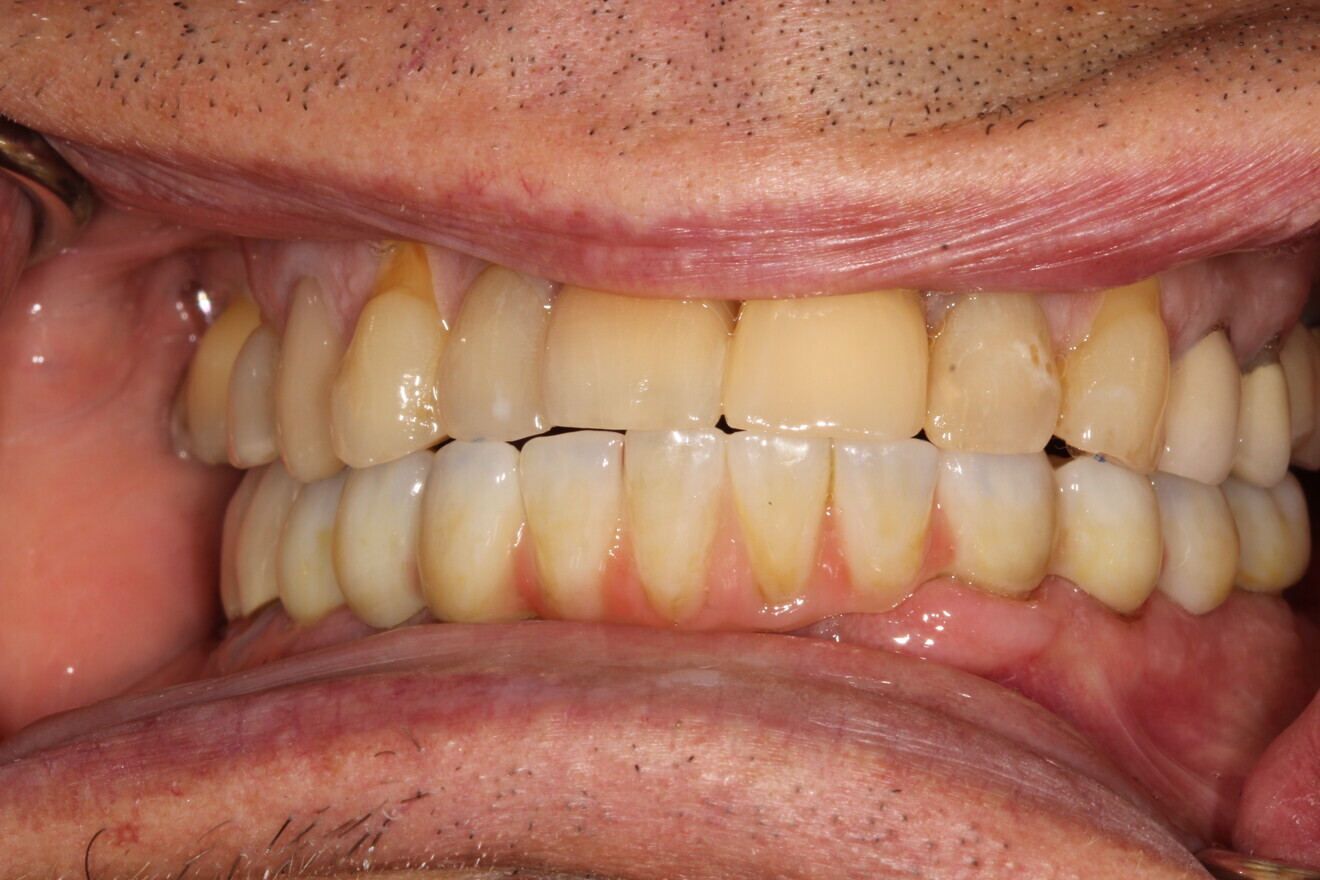

A final full-arch zirconia restoration was manufactured, and the final seating was verified with radiographs (Fig. 17) and cemented with PANAVIA SA Cement Universal (Kuraray Noritake Dental). The patient returned two weeks later for an occlusion check and adjustment along with an oral hygiene check. Pink firm gingiva around all the implants was noted such that it was even difficult to get a probe into the sulcus (Fig. 18).

Figs. 18a & b: Final restoration in function.